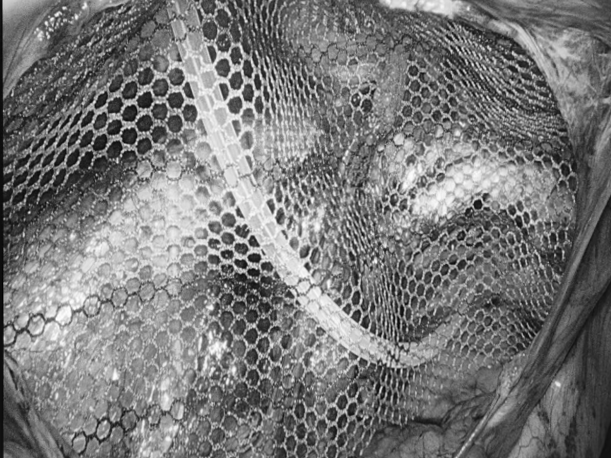

直肠脱垂是指直肠壁的一部分或全层向下移位,最终可能脱出肛门外的疾病。它并非肿瘤,但在老年人、多次分娩的女性、长期便秘或慢性咳嗽等腹压增高人群中较为常见。 【关键诱因与表现】 直肠脱垂主要因盆底肌肉、韧带等支撑结构松弛,加之长期腹压增高(如用力排便、慢性咳嗽、排尿困难)诱发。患者常感肛门坠胀或异物感,典型表现为排便或久站后有柔软肿物自肛门脱出,初期或可自行缩回,后期常需手法复位,并可伴排便困难、不尽感、肛门黏液或血性分泌物、潮湿瘙痒,严重者可能出现排便控制困难。 【治疗选择因人而异】 保守治疗(轻度或早期): 核心是消除诱因: 积极改善便秘(高纤维饮食、充足饮水、必要时遵医嘱用药)、控制咳嗽、解决排尿困难。 生活方式调整: 避免久蹲、久站、负重及用力排便。 盆底肌锻炼(凯格尔运动): 坚持锻炼有助于增强盆底支撑力。 及时复位: 轻柔地将脱出部分复位,防止卡住肿胀。 手术治疗(中重度或保守无效): 当脱垂严重影响生活、难以复位、反复出血或出现排便失禁等情况时,医生会评估手术的必要性。 手术目标是修复薄弱的支撑结构,将直肠固定在正常位置。有多种手术方式(包括微创方法),医生会根据个体情况选择最合适的方案。 【重在预防与管理】 预防的关键在于减少腹压增高因素: 1.保持大便通畅,避免用力排便。 2.积极治疗慢性咳嗽、前列腺增生等导致腹压增高的疾病。 3.坚持规律进行盆底肌锻炼。 4.维持健康体重,避免长期重体力劳动。 直肠脱垂虽然带来不适,但通过及时就医、明确诊断并接受规范治疗(包括生活方式调整和必要的医疗干预),多数患者的症状可以得到有效控制,生活质量显著提升。如有相关疑虑,建议咨询肛肠专科医生。 注:部分图片来源于网络,如有侵权,请联系删除。 贵州航天医院普外科专家简介 高大勇 普外科(肛肠外科)学科带头人、名誉主任,主任医师、教授 临床擅长:对中西医结合诊治肛肠学科各种常见病、多发病及疑难杂症等具有丰富的临床经验。 原遵义市第一人民医院(遵义医科大学第三附属医院)、遵义市中医院肛肠科主任。中华中医药学会肛肠分会常委,全国中医肛肠学科名专家,中国健康促进与教育协会肛肠分会常委,中国康复医学会肛肠疾病康复专业委员会常委,中国民间中医医药研究开发协会肛肠分会副秘书长,中国医师协会中西医结合肛肠医师专业委员会常委,国家二级心理咨询师,贵州省第一批中医名医工作指导老师,遵义市名中医,遵义市肛肠学会会长,遵义市肛肠质控中心名誉主任,遵义市中西医结合学会名誉会长,遵义市健康科普专家,原贵州省中西医结合学会肛肠分会副主任委员、贵州省中医肛肠质控中心副主任、遵义市医学会医疗鉴定委员会专家、遵义市卫生系列高评委。发表论文30余篇,主编和参编医学著作5本,主持省级科研课题2项、市级科研课题2项、院级科研课题1项。 梁 跃 中共党员,普外科党支部书记、主任,主任医师 临床擅长:对普外科各类肿瘤手术具有丰富的临床经验。 毕业于遵义医学院,遵义市医学会小儿外科学分会常务委员,遵义市肛肠协会理事,遵义市医学会核医学分会(第二届)委员会委员;荣获第三期“黔医人才计划”优秀学员称号;主持市级课题1项,完成省级课题1项,在国内各类刊物上发表论文10余篇。 钱科洪 民盟盟员,普外科副主任医师 临床擅长:从事普外科临床工作30余年,对各类普外科疾病的诊治、乳腺、甲状腺、胃十二指肠、结直肠等疾病及疑难杂症具有丰富的临床经验。 毕业于遵义医学院临床医疗系,2009年前往中山大学附属第一医院微创外科进修学习,在国内各专业期刊发表论文数篇。 贵州航天医院普外科简介 基本情况 贵州航天医院普外科成立于1968年,前身属于航天部O61基地3417医院外一科,1998年3417医院、3427医院合并后更名为普外科,下设胃肠外科、肛肠外科2个亚专业科室,拥有在全市较为先进的专科设备和技术,是中国疝病专科联盟单位,贵州医科大学附属医院胃肠外科专科联盟单位。开放床位40张,配备医护人员21人。 专科特色 普外科致力于胃肠及肛肠疾病的外科临床诊治及科研,以腹腔镜微创外科技术为本,形成以快速康复治疗胃肿瘤、结直肠肿瘤、小肠肿瘤、直肠脱垂、肥胖病、急腹症、各类疝、痔、瘘等专科特色,同时注重胃肠疾病尤其是结直肠恶性肿瘤的基础研究和临床转化研究,总体诊断和治疗水平在区域同级医院居于领先水平。 开展手术:腹腔镜下胃癌根治术,腹腔镜下袖状胃切除术,腹腔镜下胃肠道间质瘤切除术,腹腔镜下结、直肠癌根治术,胃癌、结直肠癌的精准治疗,腹腔镜下小儿疝气、成人疝修补术,腹腔镜下阑尾手术,内痔的硬化注射治疗及痔疮的微创治疗:ATH、PPH、TST,直肠脱垂的各种手术治疗,难治性伤口VSD技术,鼻胃肠管、肠梗阻导管置入术,肛肠术后间歇性导尿技术,并引进了中医适宜技术,也为各种化疗患者提供输液港安装,提高患者就医体验。 腹腔镜下腹股沟疝 无张力修补术 腹股沟疝里金斯坦(Lichtenstein)手术 PPH微创术治疗环状混合痔 黏连性或炎性肠梗阻-肠梗阻导管 腹腔镜袖状胃切除 腹腔镜阑尾切除术 腹腔镜阑尾肿瘤切除术 腹腔镜下结肠癌根治术 诊疗范围 胃肿瘤、结直肠肿瘤、小肠肿瘤、肥胖症、各类急腹症、腹部外伤、腹壁疝、便秘、直肠脱垂、痔疮、肛瘘、肛裂等胃肠、肛肠外科疾病。 END